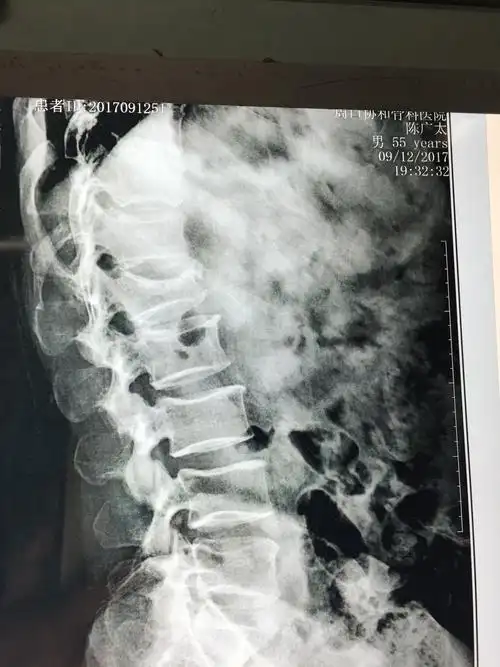

此片腰椎过伸过曲位片,腰1考虑为压缩性骨折(陈旧性)